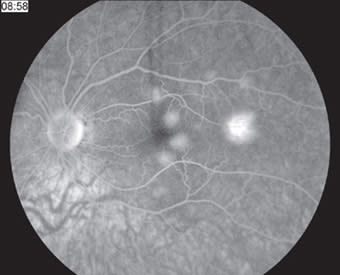

In 1968, Gass first described this self-limited inflammatory condition, acute posterior multifocal placoid pigment epitheliopathy (APMPPE), in which multiple white-yellow placoid lesions develop at the level of the retinal pigment epithelium and cause a rapid reduction of central vision in otherwise healthy young adults. The yellow-white retinal lesions fade to patches of RPE atrophy and hypertrophy, though all phases may be observed simultaneously. The visual changes typically recover within three weeks, though recovery may be limited with foveal involvement. Characteristic early hypofluorescence and late hyperfluorescence on fluorescein angiography (Figures 7 and 8) may be related to choroidal ischemia and a resultant delay in filling. Given an association with HLA-B7 and HLA-DR2, an immune-mediated mechanism and genetic susceptibility have been proposed. RP

Figure 8. At presentation, late-phase fluorescein angiogram showing delayed hyperfluorescence of RPE lesions.